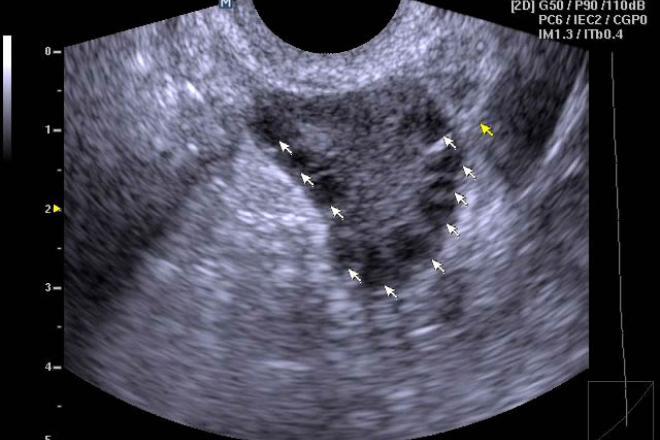

Se presenta un caso de carcinoma en tejido mamario ectópico axilar: Una paciente femenina de 38 años de edad, quien consultó por aumento de volumen y presencia de un nódulo en la región axilar de un año de evolución y punción aspiración por aguja fina